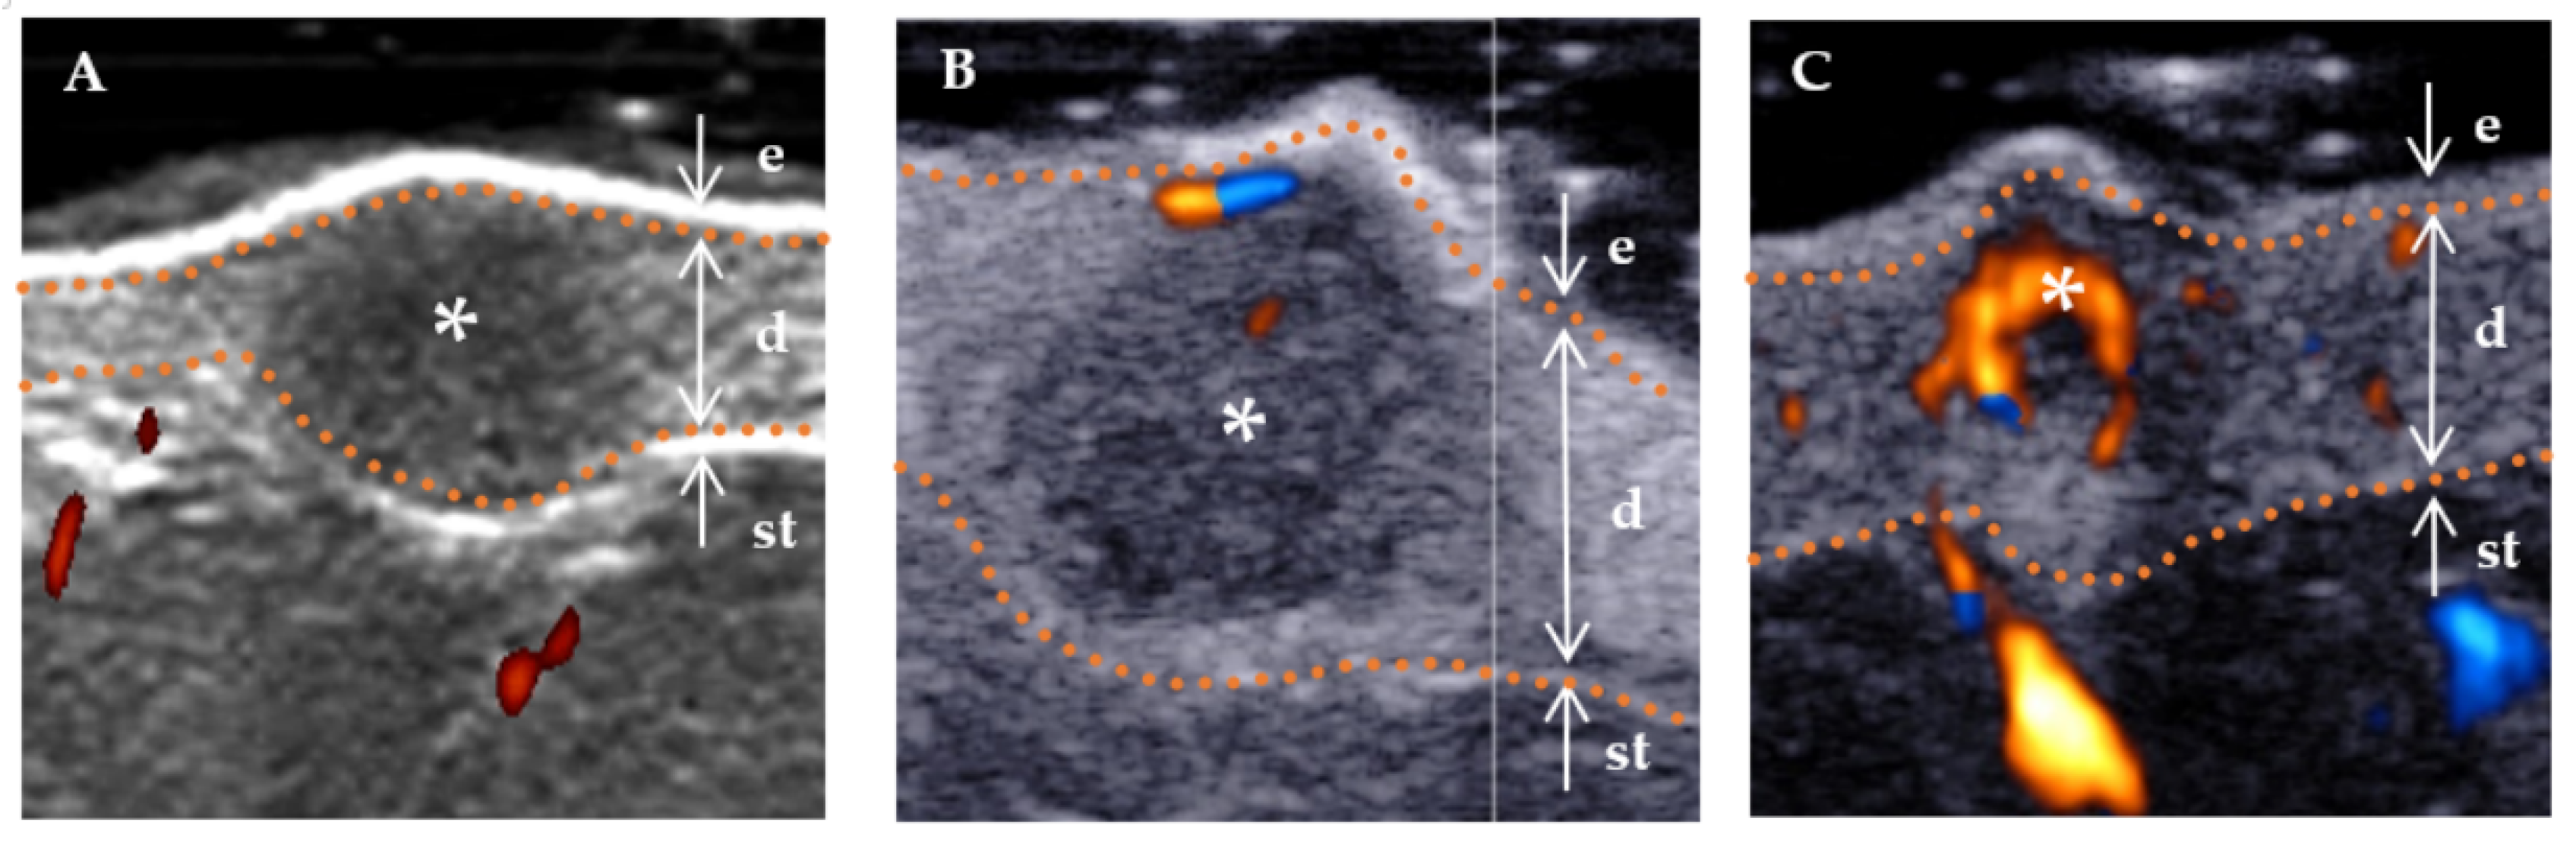

| Doppler vascularity pattern, n (%) | 0.038 * | ||

| Absent | 6 (35.3%) | 23 (69.7%) | |

| Sparsity | 8 (47.1%) | 9 (27.3%) | |

| Profusion | 3 (17.6%) | 1 (3.0%) |

| Internal echogenicity, n (%) | 0.004 * | ||

| Homogenous | 4 (23.5%) | 27 (81.8%) | |

| Heterogenous | 13 (76.5%) | 6 (21.2%) | |